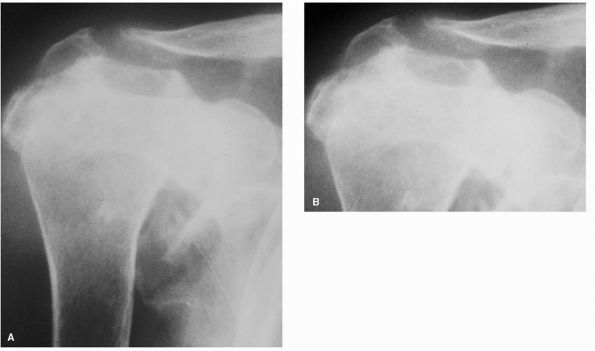

exhibiting only minimal findings with more extensive changes late in

the course of disease. Plain radiographs may reveal only osteopenia of

the humeral head and glenoid. Symmetrical

marginal

erosions along the inferior humeral head and subchondral cysts develop

and may eventually involve large portions of the head. Glenoid

destruction occurs with disease progression demonstrating central or

peripheral erosions (Figure 12-14).

Osteosclerosis and osteophytosis is uncommon in RA and typically

reflects quiescence of the inflammation and development of secondary

osteoarthritis.

FIGURE 12-14. (A) Anteroposterior and (B)

axillary views demonstrating rheumatoid arthritis of the glenohumeral joint. Narrowing of the joint space, large subchondral cysts, and medialization of the glenoid are typical. Note the absence of large peripheral osteophytes commonly seen with osteoarthritis. |